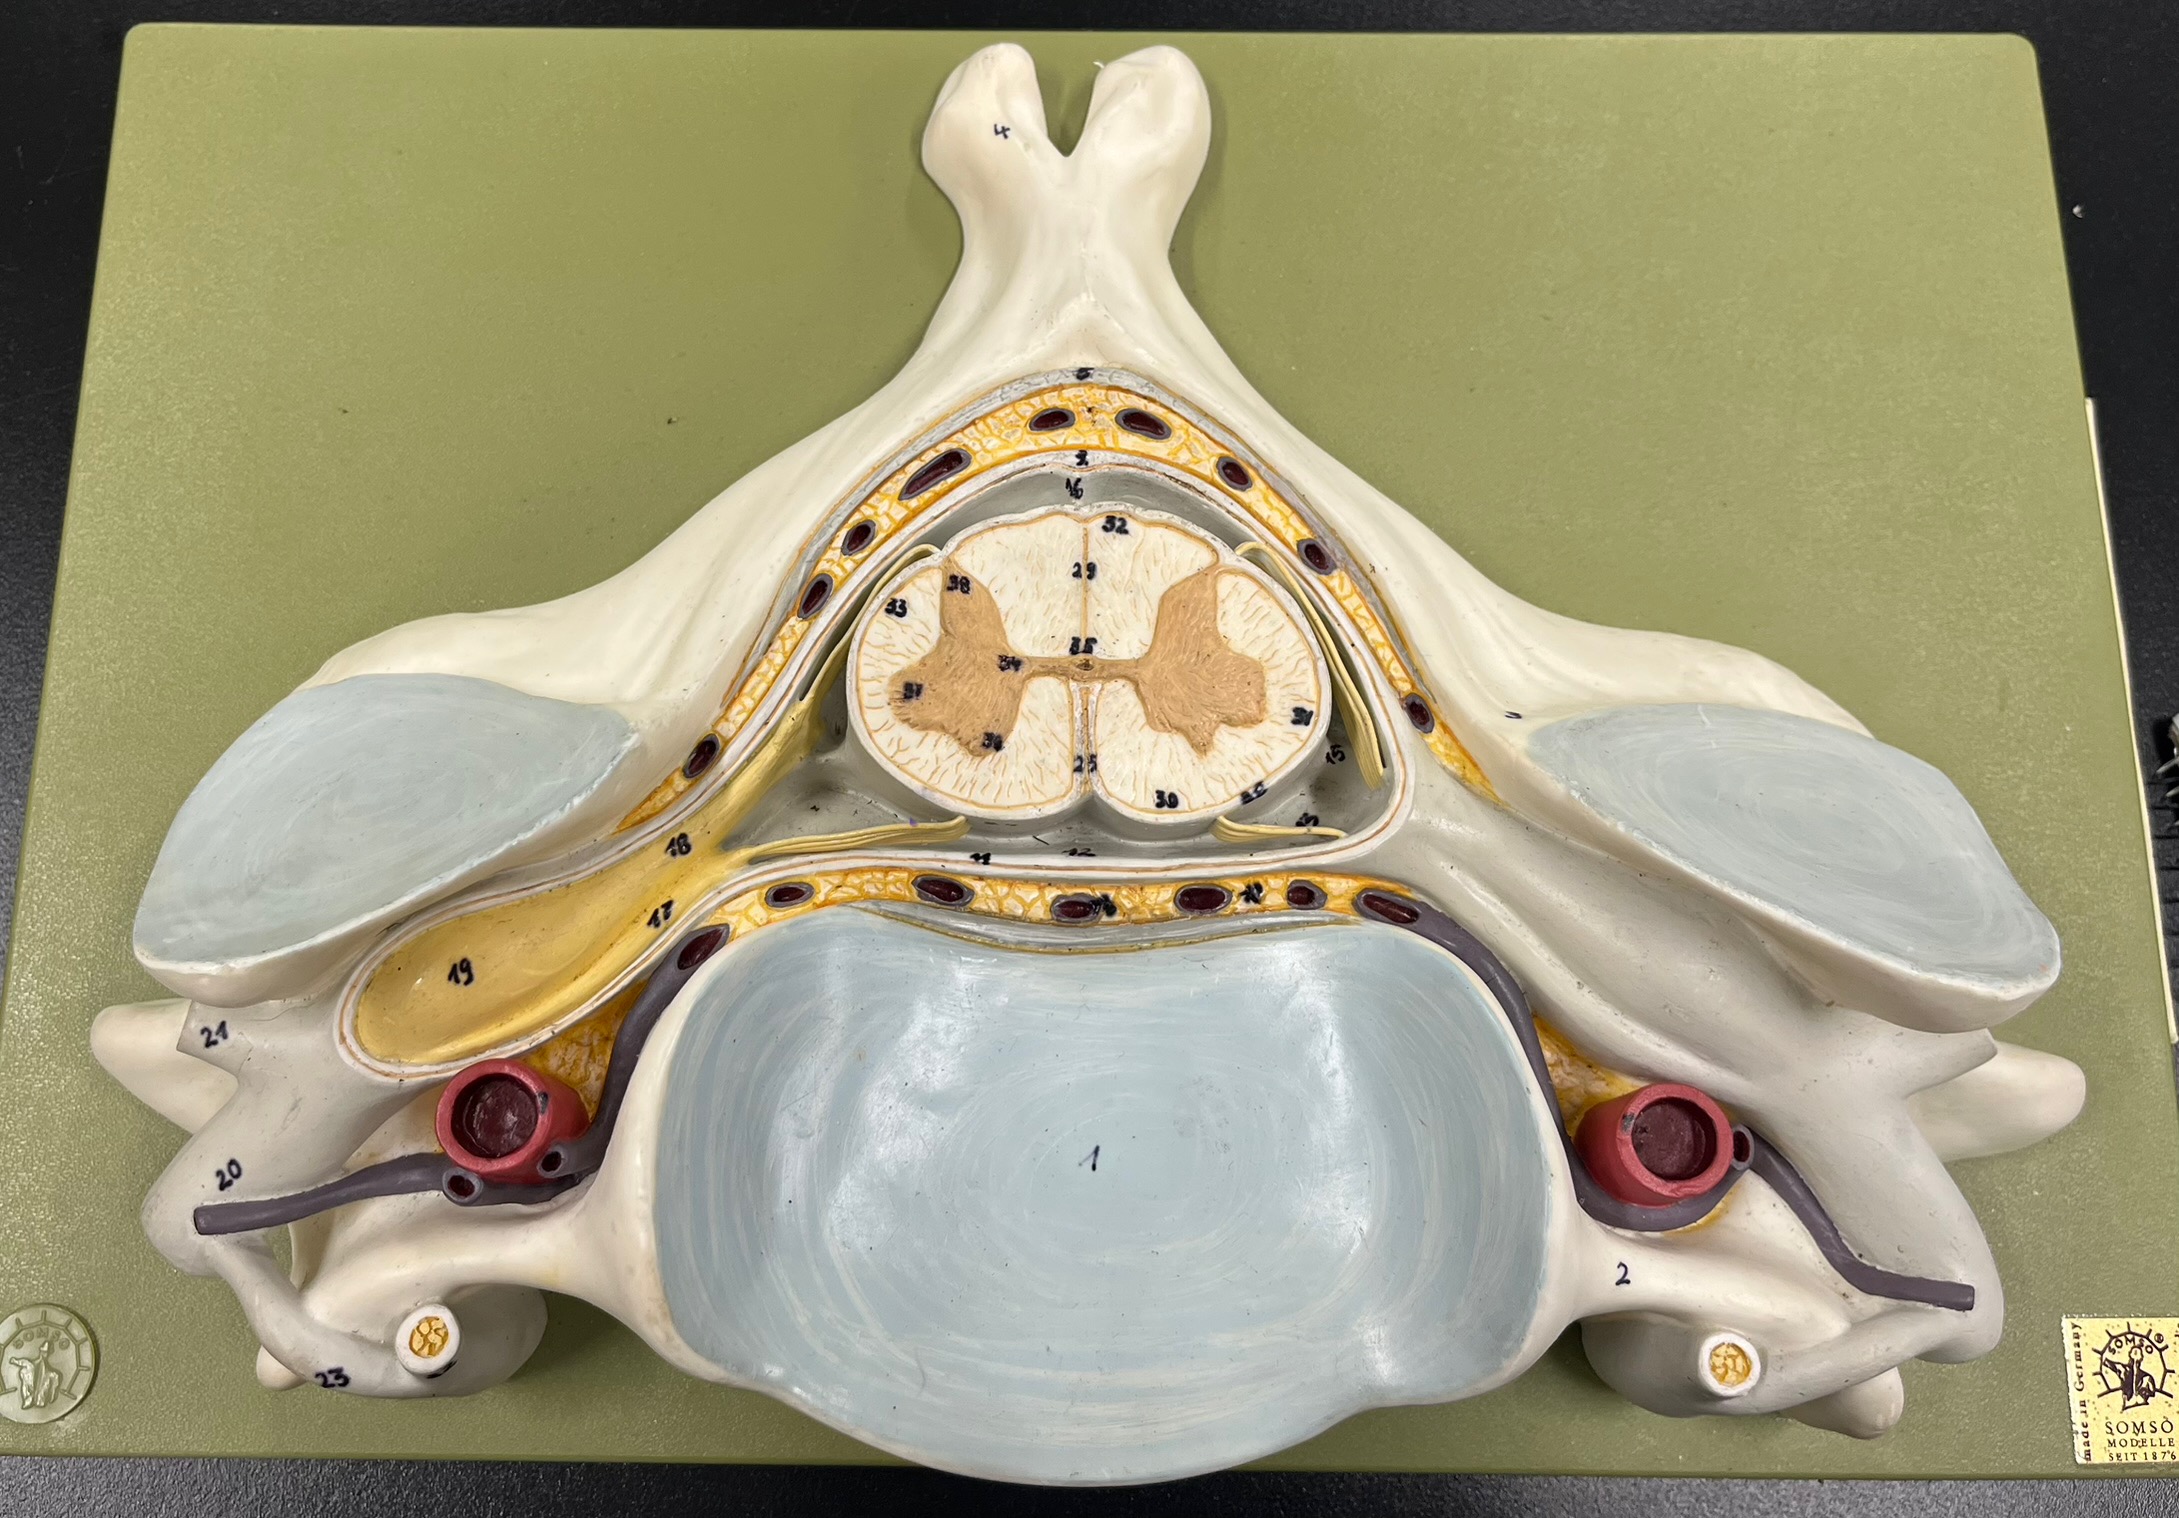

epidural space

dura mater

subdural space

arachnoid mater

subarachnoid space

pia mater

denticulate ligaments

What is the groove here?

anterior median fissure

posterior median sulcus

posterior (dorsal) horn

posterior (dorsal) horn; R—>L

anterior (ventral) horn

lateral horn (selected models)

gray commissure

central canal

anterior column

lateral column

posterior column

white commissure

posterior (dorsal) root ganglion

What is the bulb here?

posterior (dorsal) root ganglion

posterior (dorsal) root

posterior (dorsal) root

anterior (ventral) root

anterior (ventral) root

dorsal ramus

dorsal ramus

ventral ramus

ventral ramus

rami communicantes

rami communicantes

sympathetic chain ganglia

sympathetic chain ganglia